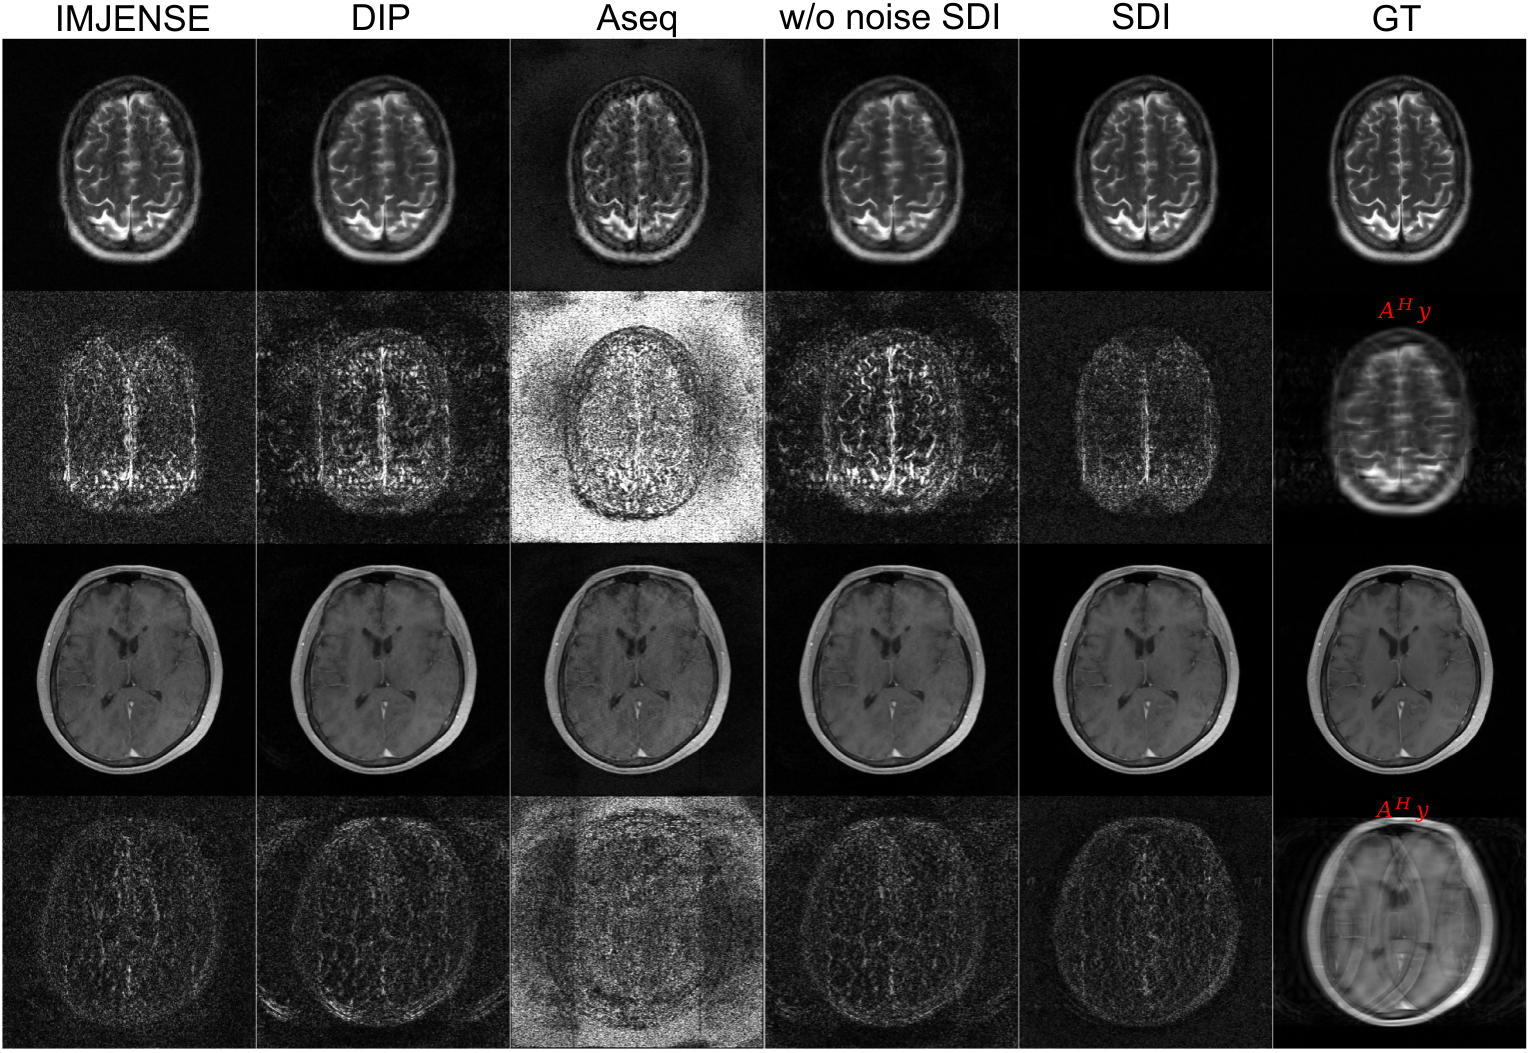

MRI reconstruction: Reconstruction from 4\(\times\) undersampled k-space with 20 ACS lines using different methods (\(\mathcal{A}^H\mathbf{y}\),IMJENSE, DIP, Aseq, w/o noise SDI, SDI) and corresponding error maps are shown.